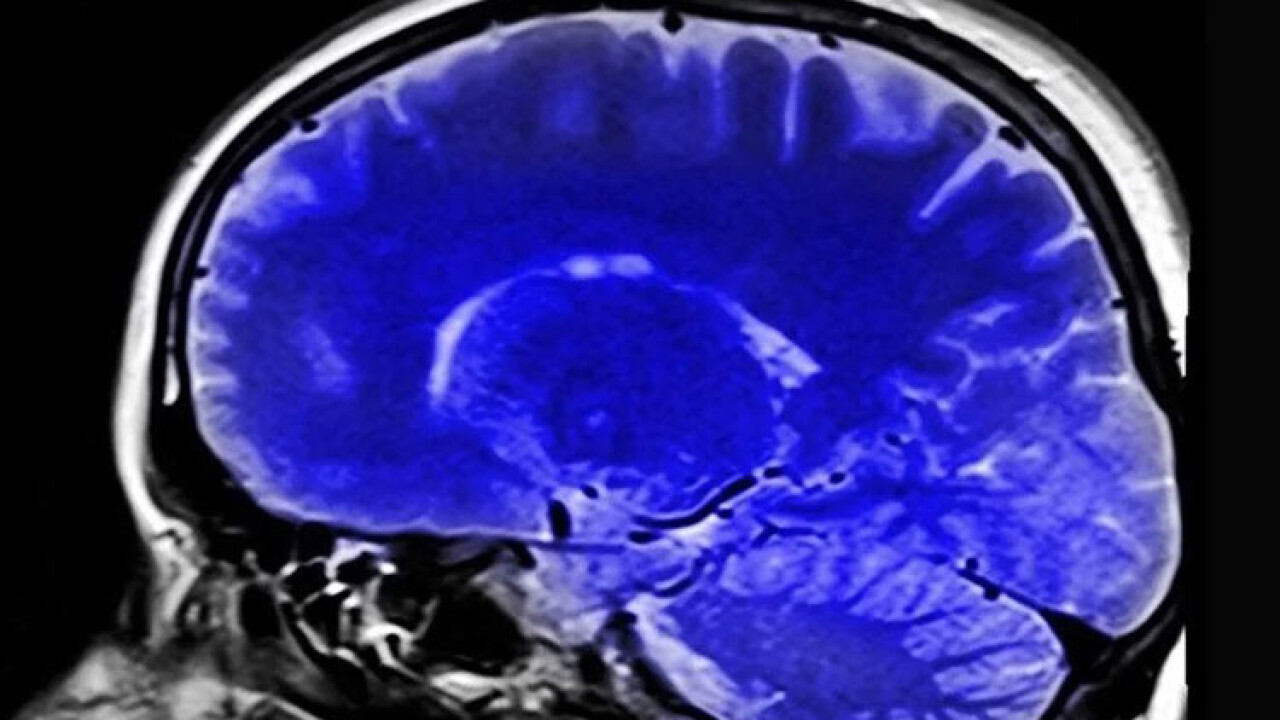

ABD'de yapılan araştırma, ağrıların beyindeki kaynağına ilişkin yeni bulgular elde edilerek kronik ağrı çeken hastalara umut olunabileceğini ortaya koydu.

Nature Neuroscience dergisinde yayımlanan yeni araştırma kapsamında San Francisco şehrindeki California Üniversitesinden bilim insanları, yapay zeka algoritması kullanarak makine öğrenimi araçlarıyla topladıkları verileri analiz etti.

Bireylerin yaşadığı acıyı hafifletmek amacıyla potansiyel çözümlerin incelendiği araştırmada inme veya ampütasyon sonrası oluşan kronik ağrı bozukluklarının beyindeki yansımalarına dair bulgular elde edildi.

Araştırmacılar, katılımcıların kronik ağrı düzeylerine bağlı olarak tepkilerinin yansıdığı düşünülen beynin "anterior singulat korteks (ACC)" ve "orbitofrontal korteks (OFC)" adlı iki bölgesindeki aktivite değişikliklerine odaklandı.

Üçü inme sonrası, biri de kesilmiş olmasına rağmen sanki uzvu varmış gibi ağrı şikayeti bulunan katılımcılara ACC ve OFC'lerindeki aktivite değişikliklerini tespit etmeyi hedefleyen elektrotlar, cerrahi müdahaleyle yerleştirildi.

Katılımcılardan gün içinde birkaç kez yaşadıkları acıyı nasıl derecelendirdikleri, duygusal olarak nasıl hissettirdiği gibi soruları yanıtlamaları istendi, bu sırada hastaların ACC ve OFC'lerindeki aktivitenin anlık görüntüleri kaydedildi.

Beyin aktivitelerini ortaya çıkarmaya yönelik ilk çalışma

Araştırmacılar, elde ettikleri sonuçlarla kronik ağrının beyinde nasıl belirdiğine dair daha derin bir anlayış kazanarak beyin aktivitelerini modüle etmek amacıyla yenilikçi stratejiler geliştirmeyi ve bu acı verici durumdan şikayetçi olanlara ihtiyaç duydukları rahatlamayı sağlamayı umduklarını söyledi.

Bunun, "ağrı algısının altında yatan beyin aktivitelerini ortaya çıkarmaya yönelik ilk çalışma" olduğu bilgisini veren araştırmacılar, ağrının beyindeki kaynağının belirlenmesinin, kronik ağrıdan kaynaklanan acıyı hafifletmek için beyin aktivitesini değiştirebilen yeni terapilerin geliştirilmesini sağlayacağını kaydetti.

"Ağrı hakkında anlayamadığımız pek çok şey var"

ABD'nin California Üniversitesi Anestezi ve Nörolojik Cerrahi Bölümü'nden Doç. Dr. Prasad Shirvalkar, çalışmayla ilgili "Düşündüğümüzde ağrı, yaşadığımız en temel tecrübelerden biridir. Buna rağmen halen ağrı hakkında anlayamadığımız pek çok şey var." açıklamasında bulundu.

Shirvalkar, akut ağrılar tecrübe edildiğinde MR taramalarıyla beynin ACC ve OFC bölgelerindeki yansımalarını görebildiklerini belirterek, buradan yola çıkarak beyindeki ACC ve OFC bölgelerinin kronik ağrı oluştuğunda nasıl tepki verecekleriyle ilgilendiklerini kaydetti.

Ağrının zamanla nasıl değişeceğini merak ettiklerini vurgulayan Shirvalkar, yüksek derecedeki kronik ağrı konusunda beynin ne tür işaretler vereceğine, beynin ağrıyı tahmin edip edemeyeceğine odaklandıklarını dile getirdi.